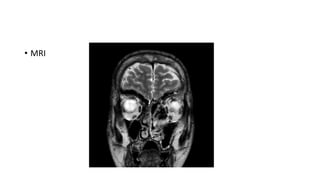

• MRI

Hypointensity on T1WI and T2WI is the most common finding.

Indications of MRI :

1. When diagnosis is uncertain

2. When there is rare intracranial or intraorbital complication